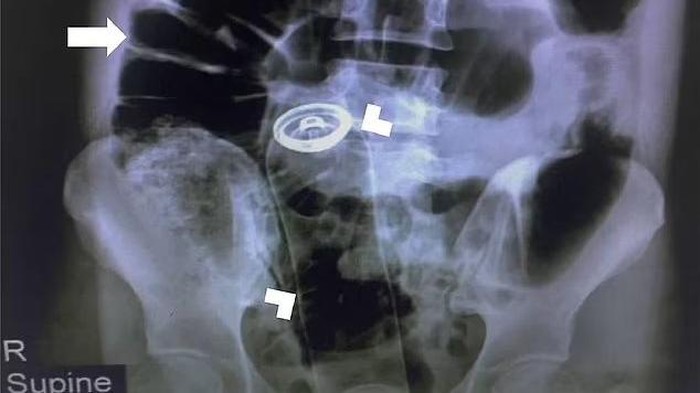

Ketika menjalani pemeriksaan dubur standar, pria itu dilaporkan mengalami rasa sakit yang luar biasa. Oleh karenanya, tim medis terpaksa menggunakan x-ray untuk menemukan kaleng itu telah masuk ke jalur pencernaannya.